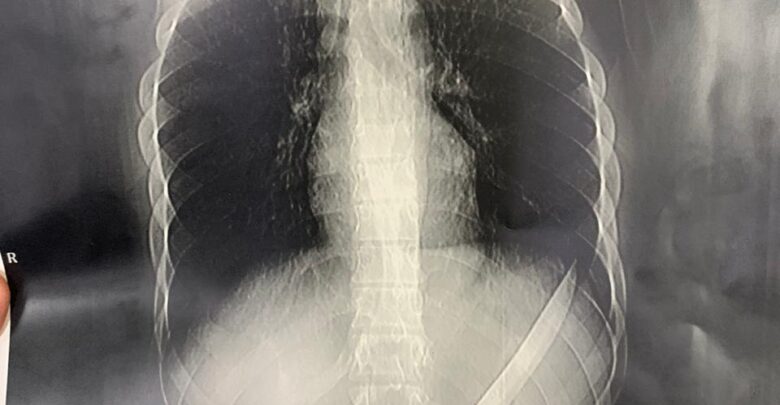

وأوضح أن المريض حضر لمستشفى المنصورة الدولي يعاني من آلام شديدة بالبطن وبعمل الأشعات والفحوصات تبين وجود جسم غريب.

وأضاف وكيل وزارة أن الفريق الطبي تمكن من إجراء عملية جراحية لاستخراج الجسم الغريب حيث تبين أنه سكين مطبخ وقد تكللت العملية بالنجاح وخرج المريض بحالة مستقرة.